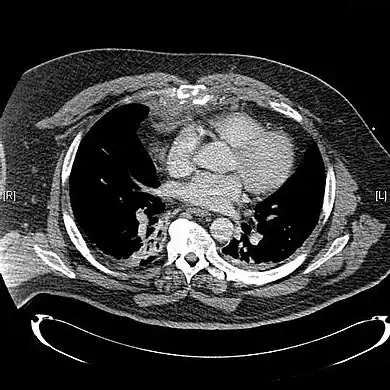

CT scan showing a comminuted sternal fracture.[14]

X-rays of the chest are taken in people with chest trauma and symptoms of sternal fractures, and these may be followed by CT scanning.[12] Since X-rays taken from the front may miss the injury, they are taken from the side as well.[13]